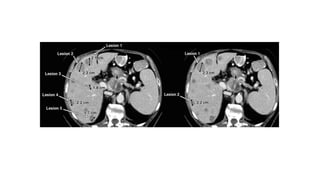

Identify the lesion

• Target lesion :

• Maximum 5 lesions

• 2 lesions per organ

• Lesion with longest diameter

• Easy for repeated reproducible measurement